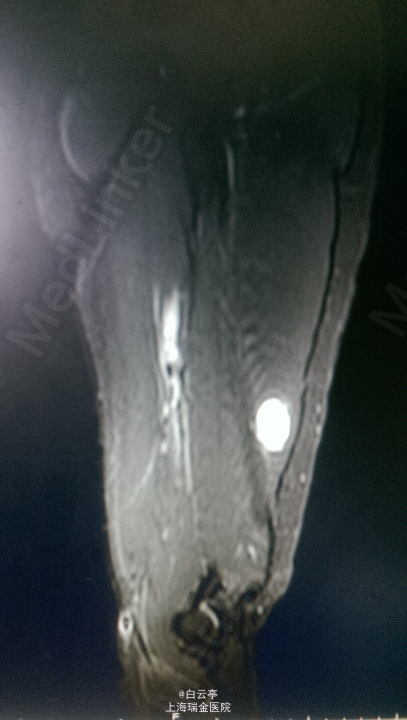

查体: 右上臂皮肤颜色正常,右上臂后侧中下1/3处触及一个3*3cm大小包块,质韧,与周围分界清楚,无波动,活动度良好。右肩关节和右肘关节活动良好,右手感觉正常。左侧上肢活动正常。 辅查: 1. 超声报告示:右上臂肌层实质性占位,性质待定。2. MR示:右上臂中下段后方肌群内见一团块异常信号占位,血管瘤?

诊断:右上臂软组织肿物。择期行软组织肿块切除术。术中切取软组织送病检,病理诊断为右上臂肌肉内血管瘤。